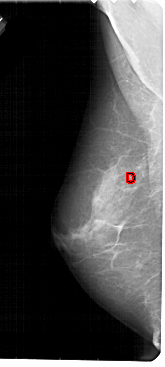

A_1946_1.LEFT_MLO

LEFT_MLO LINES 5491 PIXELS_PER_LINE 2461 BITS_PER_PIXEL 12 RESOLUTION 43.5 OVERLAY

FILE: A_1946_1.LEFT_MLO.OVERLAY

TOTAL_ABNORMALITIES 1

ABNORMALITY 1

LESION_TYPE CALCIFICATION TYPE PLEOMORPHIC DISTRIBUTION CLUSTERED

ASSESSMENT 4

SUBTLETY 3

PATHOLOGY BENIGN

TOTAL_OUTLINES 1

BOUNDARY